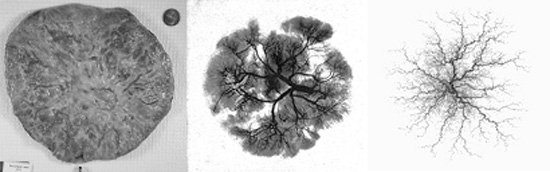

human placenta with placental vasculature and model placental vascular tree

Left to right: typical human placenta; X-ray of the placental vasculature; model placental vascular tree.

The surface of a placenta is a quintessential random shape: typically round, it is nevertheless highly variable. The variation of the surface shape is a record of adverse impacts on the development of the baby. Decrypting this record poses an exciting challenge. During “Random Shapes”, Dr. Salafia met Michael Yampolsky, an expert in Dynamical Systems from the University of Toronto. One of the striking aspects of irregular placental shapes is how symmetric they often appear. This symmetry was a clue which suggested to Salafia and Yampolsky that the variation in shape may be caused by a deviation in the branching structure of the underlying vascular tree.

To test this hypothesis, the researchers developed a dynamical model for the placental angiogenesis – the process of vascular growth. It is based on Diffusion Limited Aggregation (DLA), an important model of random fractal growth in Mathematical Physics. The DLA-based model of Salafia and Yampolsky simplifies the picture of the vascular growth, and does not fully incorporate the biochemical mechanisms driving the growth. Nevertheless, the model has successfully predicted much of the observed variability of placental shapes. The pathological shapes correspond to maternal stresses which suppress vascular growth at different moments in gestation. This is an important finding, since stresses have different effects at different times.